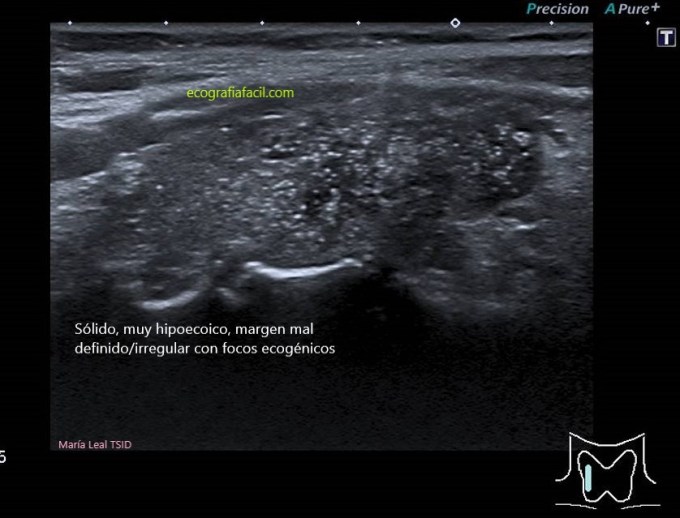

SÓLIDO:

Sólido

TI-RADS 5

Alta sospecha de malignidad (mayor del 80%)

COMPOSICIÓN: Sólida                           2

ECOGENICIDAD: Muy hipoecoica          3

FORMA: Más ancho que largo               0

MARGEN: Irregular                                 2

FOCOS ECOGÉNICOS: (puntiformes)       3

10 puntos